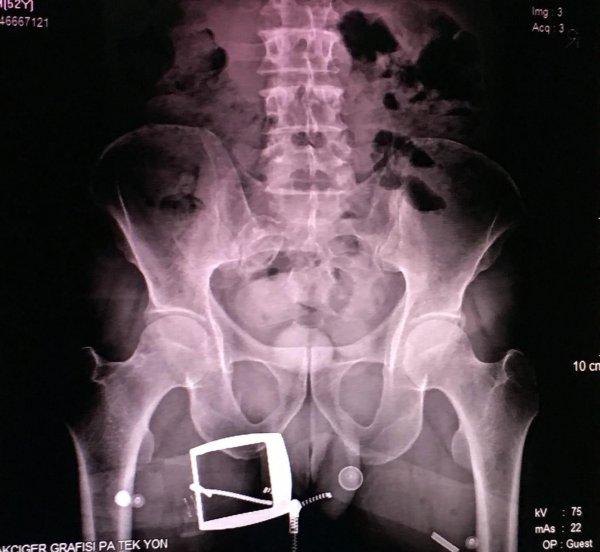

Gözaltına alınan B.H.’nin hareketlerinden şüphelenen narkotik polisi, kendisini sağlık kontrolü için hastaneye götürdüğünde röntgen çekilmesini de istedi. Röntgen filmi sonuçlarında İranlı kadının uyuşturucuyu kapsüller halinde makatına soktuğu anlaşıldı. Tıbbi müdahaleyle 4 kapsül halinde 96 gram ‘met’ ve bir kapsülde 28 gram reçine esrar çıkarıldı.